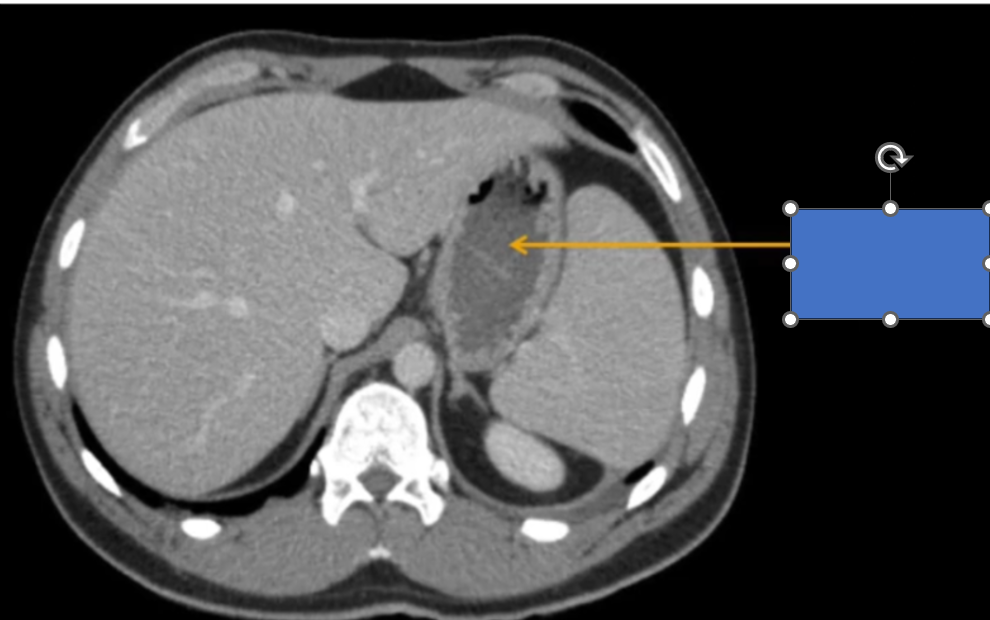

cq trong hình ?